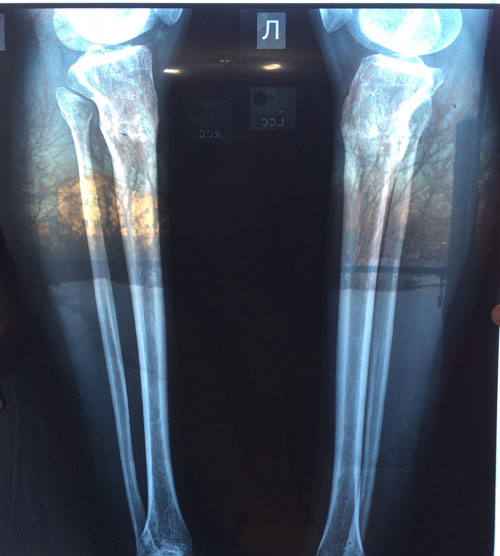

Поздравляю! Ура! Результат отличный!Sekretar Onipko писал(а):Рентген в 58 дней.

Сращение отличное, через неделю снимаем аппараты.